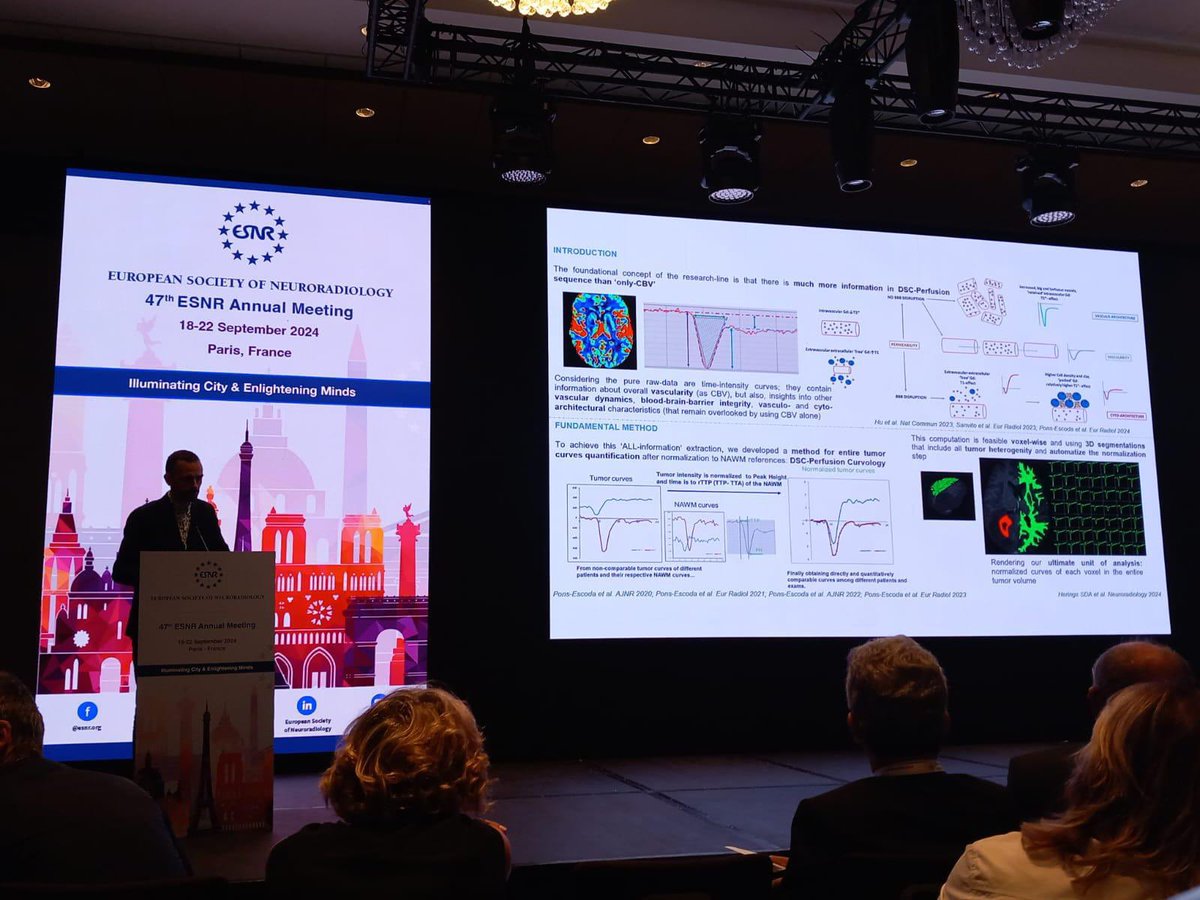

Simply so honored and thrilled by this unexpected award. Just humbled and grateful for the recognition from the European neuroradiology community. ESNR ESNRise SENR_org SERAM - Sociedad Española de Radiología Médica Hospital Universitari Bellvitge | HUB Institut de Diagnòstic per la Imatge · IDI

📣🎉Albert Pons-Escoda congratulations on recieving the 2024 ESNR Scientific Award!! You are a an INSPIRATION to those of us having the privilege to work by your side 🥳 SERAM - Sociedad Española de Radiología Médica SENR_org Hospital Universitari Bellvitge | HUB Institut de Diagnòstic per la Imatge · IDI

#Investigación 📝🩺 | Un neurorradiólogo de Hospital Universitari Bellvitge | HUB logra grandes avances con la secuencia de perfusión por #resonancia magnética #tumores redaccionmedica.com/secciones/neur…